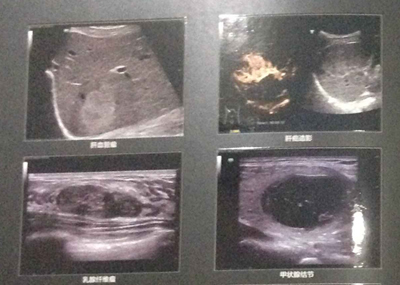

工欲善其事,必先利其器。近年来,杭州红房子妇产医院在不断加强医疗技术和服务质量的同时,还持续加大医疗设备等硬件的建设与投入。近日,斥资引进的迈瑞Reson6高端四维彩超,具有全域动态聚焦、实时弹性成像技术、自动卵泡监测等众多优点,与传统超声系统相比,不仅显著缩短了检查时间,还能在视觉上更为清晰、直观地观察到子宫、卵巢、附件等盆腔器官的异常,被誉为“妇科临床彩超检查的火眼金睛”。

据悉,目前杭州红房子妇产医院拥有“妇科微创手术黄金组合”德国WOLF宫腹腔镜、“人流术后恢复专家”ZHE保宫仪、“私密抗衰领域的法拉利”Femilift菲蜜丽私密激光等一大批现代化的医疗设备,为医院学科发展提供良好的硬件基础。随着迈瑞Reson6高端四维彩超的投入使用,将进一步提升医院的临床诊断水平,为广大女性朋友在进行妇科疾病检查时,及时、准确、高效的临床诊断提供丰富精确的诊疗依据。